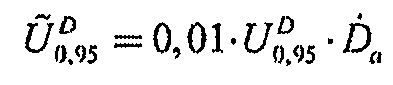

6.7. Рассчитывают абсолютную расширенную неопределенность по формуле:

,

,

(11)

6.8. Результаты измерений заносят в протокол измерений в виде:

,

,